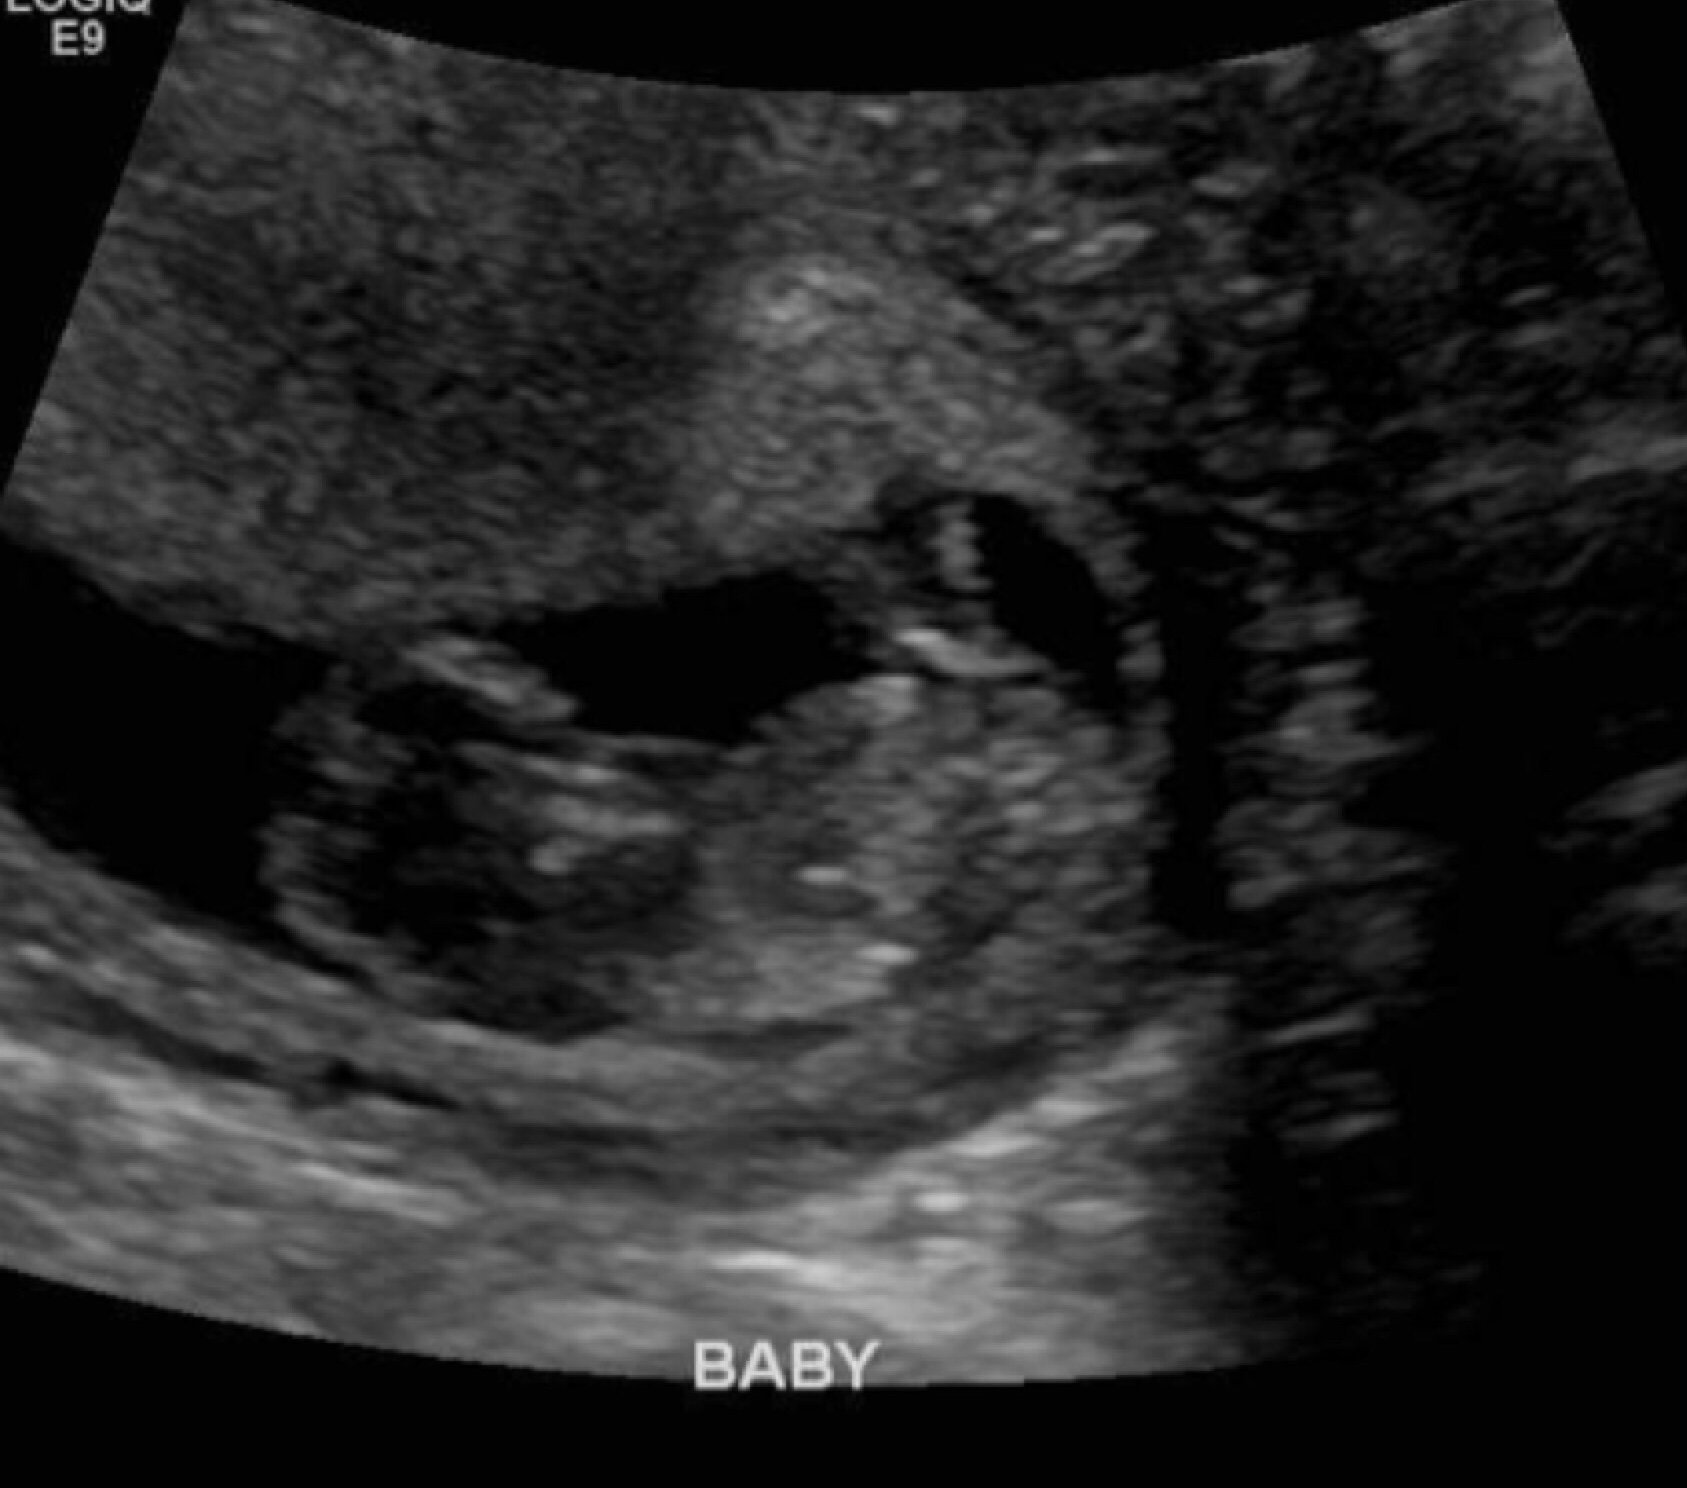

Little Dot is absolutely fine, doing perfect. Heartbeat of 167. Wiggling around and waving. Bleeding apparently might just be a *thing* for me throughout pregnancy. I can't express the amount of relief. Stop scaring your momma LO!!!